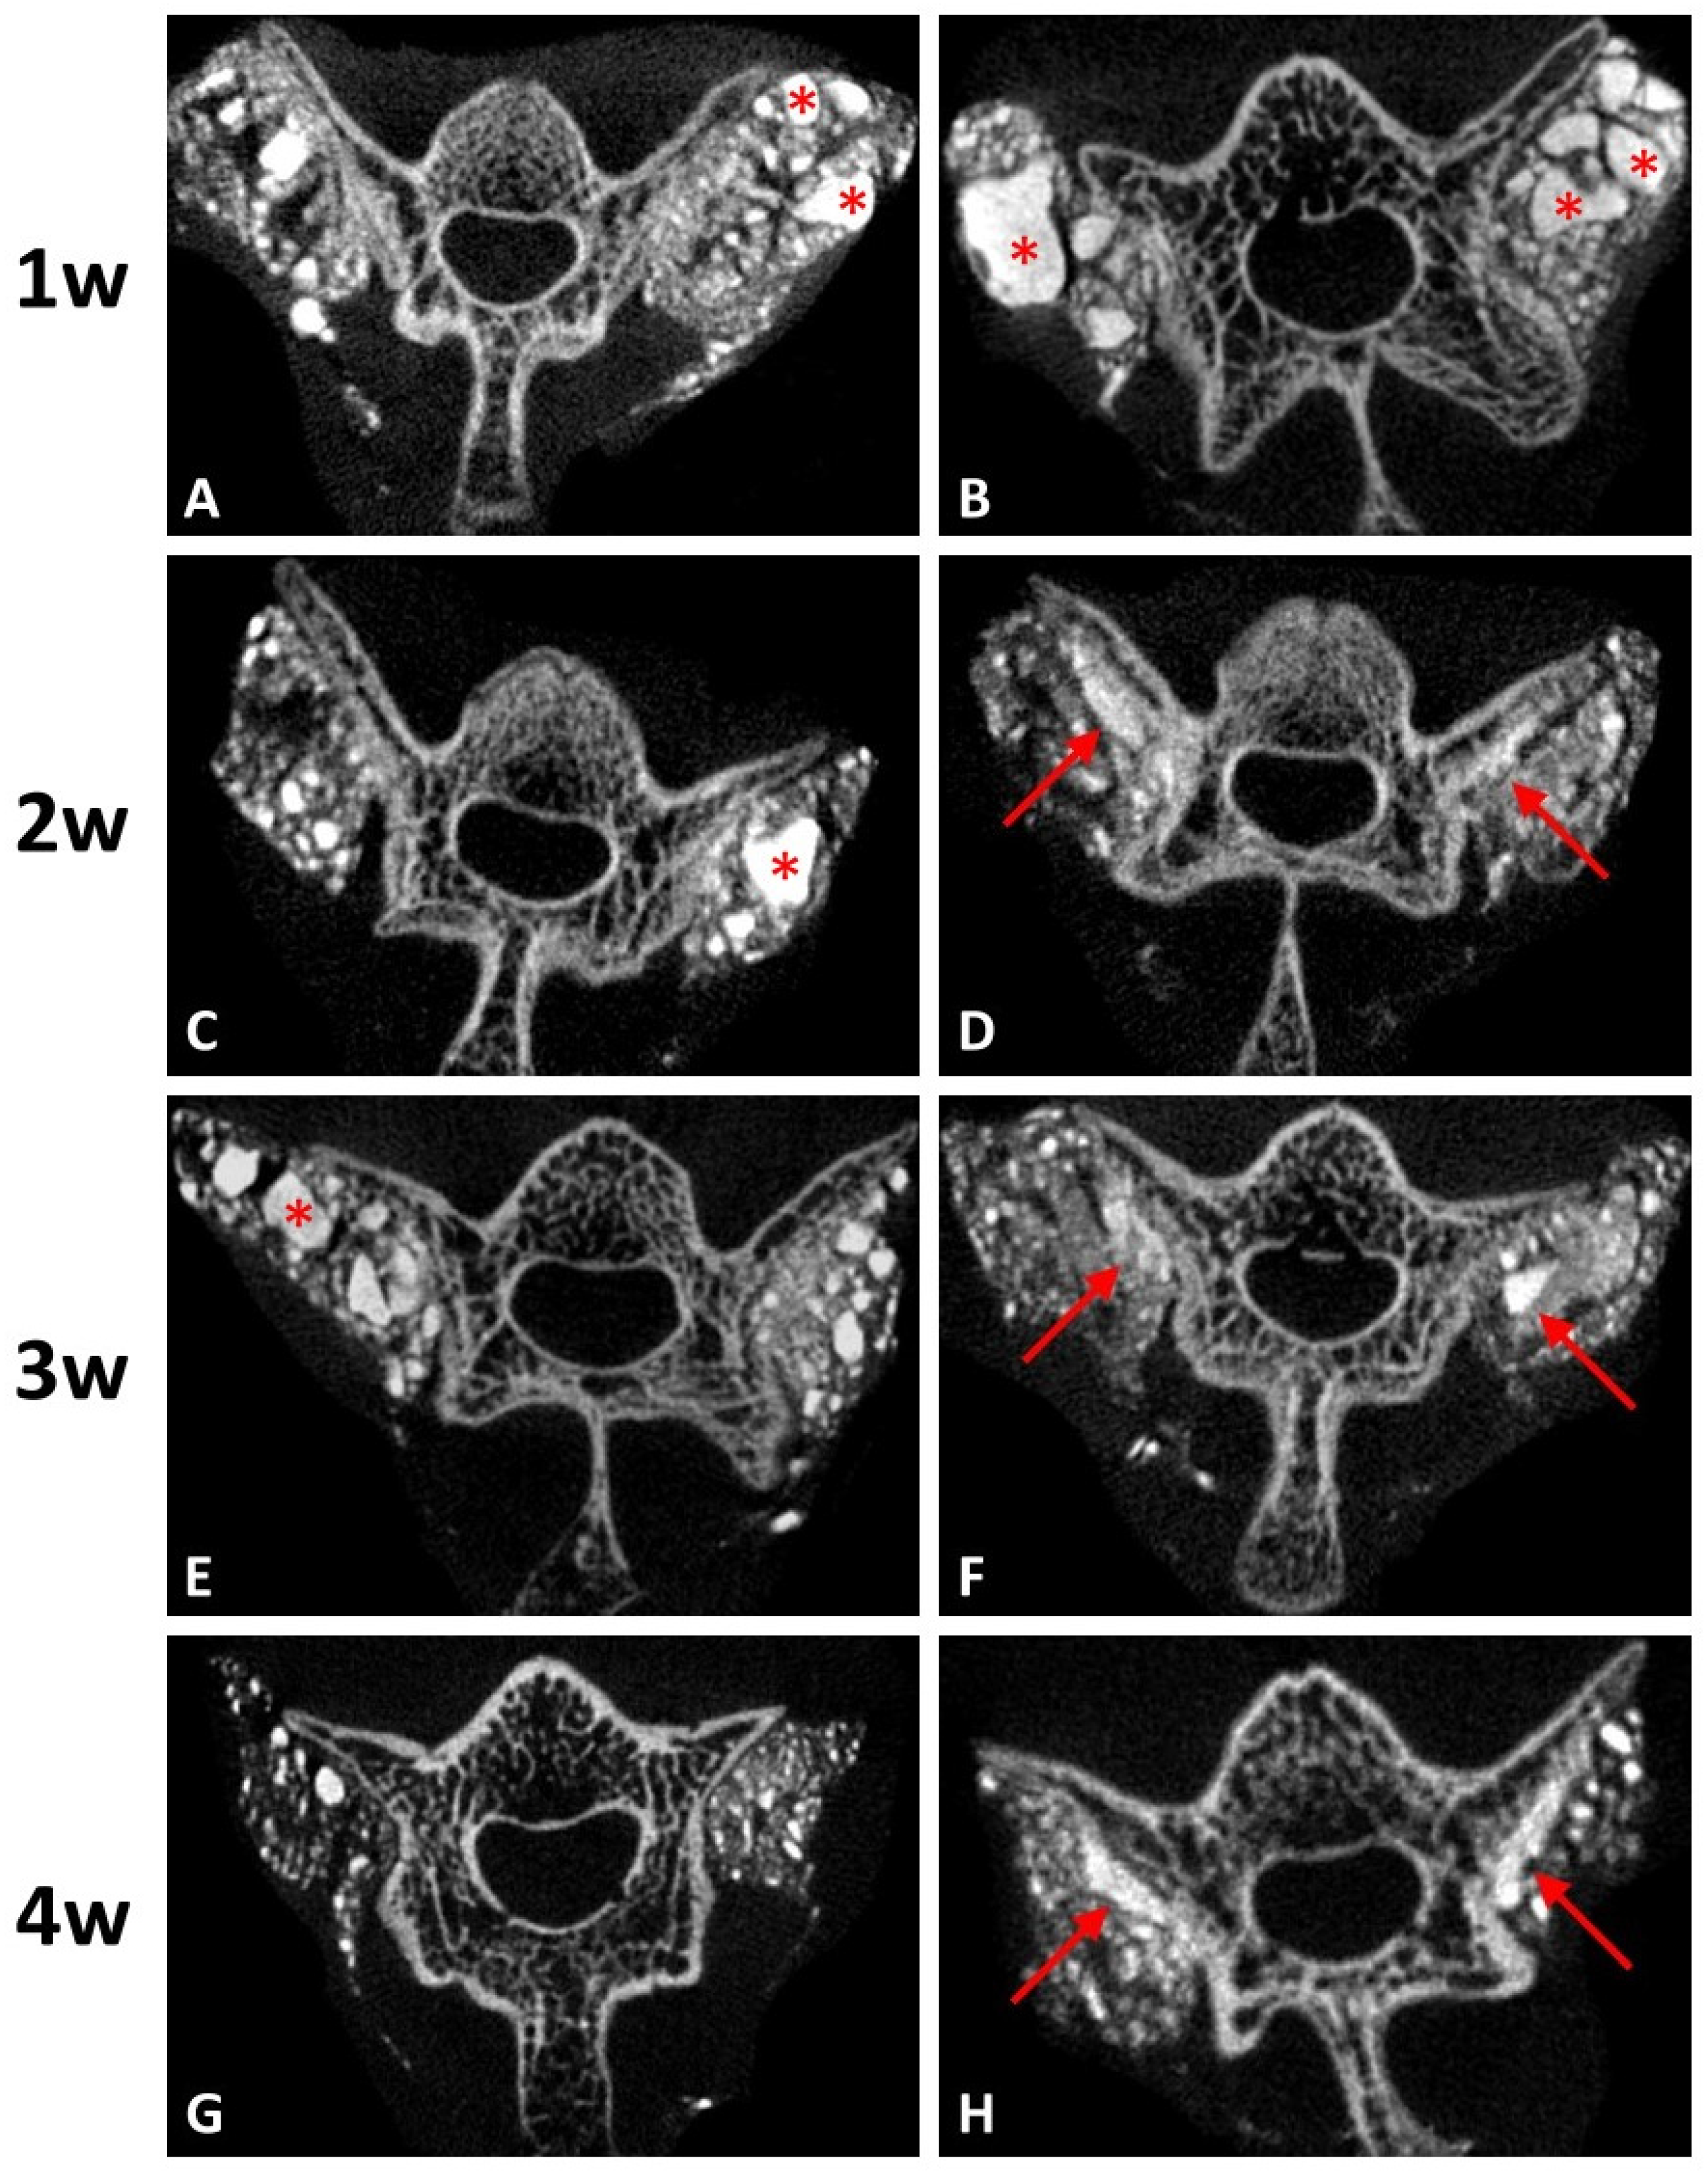

3.3.1. Radiographic Evaluation

The results of the in vitro study showed that the DCP-rich CPC supplemented with 0.4 mL collagen led to the highest levels of cell viability, cell attachment, and ALP staining. Therefore, the DCP-rich CPC supplemented with 0.4 mL collagen was selected for comparison with control for testing in vivo. The two materials were used in L4–L5 posterolateral fusion in SD rats. Radiographs four weeks post-operatively revealed notable fusion mass in both groups. For the DCP-rich CPC supplemented with 0.4 mL collagen group, more fusion mass was clearly observed bilaterally in the L4–L5 interspace than in the control group (Figure 4).

Figure 4. Posteroanterior radiographs after post-operative four weeks of the spines that underwent posterolateral lumbar fusion with (A) DCP-rich CPC or (B) DCP-rich CPC + 0.4 mL collagen. The arrows indicate fusion mass.